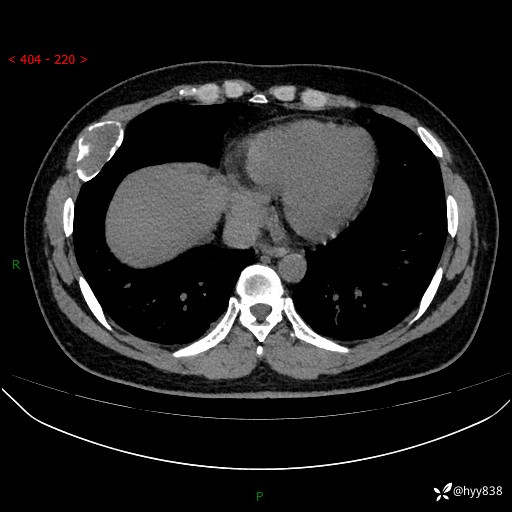

胸部CT平扫